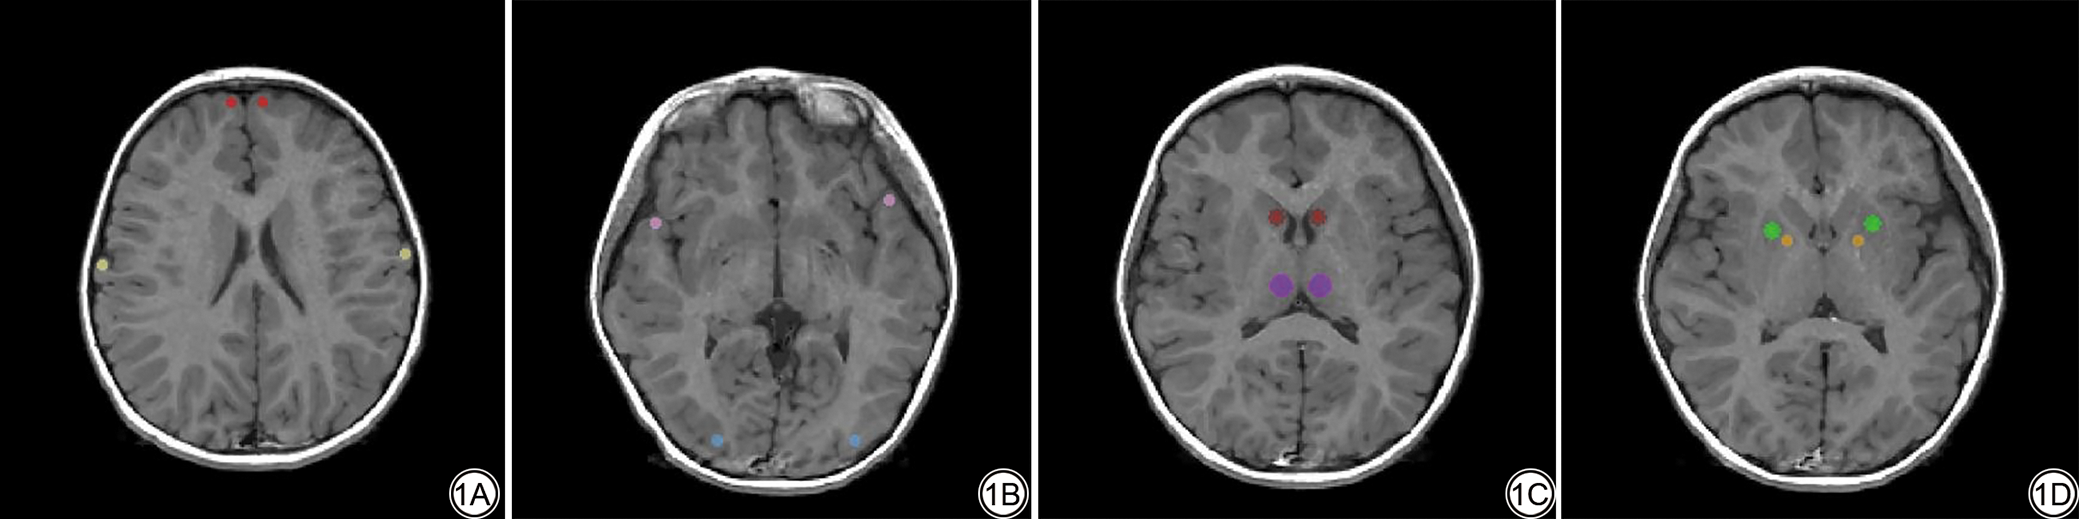

在数据处理前对图像质量进行检查,以排除采集质量差或存在明显结构异常的图像。随后,将获取的SyMRI序列图像导入后处理工作软件(SyMRI 8.0; Synthetic MR; Linkoping),生成T1、T2弛豫值和质子密度(proton density, PD)值定量图。使用ITK-SNAP3.8.0软件(www.itksnap.org),在T1、T2、PD图中进行手动勾画感兴趣区(region of interest, ROI)以获取T1、T2弛豫值和PD值,ROI的选取包括双侧额叶灰质、顶叶灰质、颞叶灰质、枕叶灰质、尾状核头、丘脑、壳核和苍白球(图1),勾画时选择圆形测量工具,避开周围结构,选择每个结构的最佳显示层面进行勾画。考虑到解剖结构的大小不同,设置勾画的ROI体素大小也不相同,具体如下:额叶灰质、顶叶灰质、颞叶灰质、枕叶灰质、苍白球设置5个体素,尾状核头、壳核设置8个体素,丘脑设置10个体素。以上测量均由两名具有10年以上神经影像诊断经验的副主任医师在不了解患者的具体分组及临床资料的情况下完成,每个ROI测量三次后取平均值。

图1  在SyMRI定量图中勾画ROI的示意图。1A:红色为额叶灰质;黄色为顶叶灰质;1B:粉色为颞叶灰质;蓝色为枕叶灰质;1C:棕色为尾状核头;紫色为丘脑;1D:绿色为壳核;橙色为苍白球。SyMRI:集成磁共振成像;ROI:感兴趣区。

Fig. 1  The schematic of ROI delineation on the SyMRI quantitative map. 1A: Red represents frontal gray matter; Yellow represents parietal gray matter; 1B: Pink represents temporal gray matter; Blue represents occipital gray matter; 1C: Brown represents head of the caudate nucleus; Purple represents thalamus; 1D: Green represents putamen; Orange represents globus pallidus.